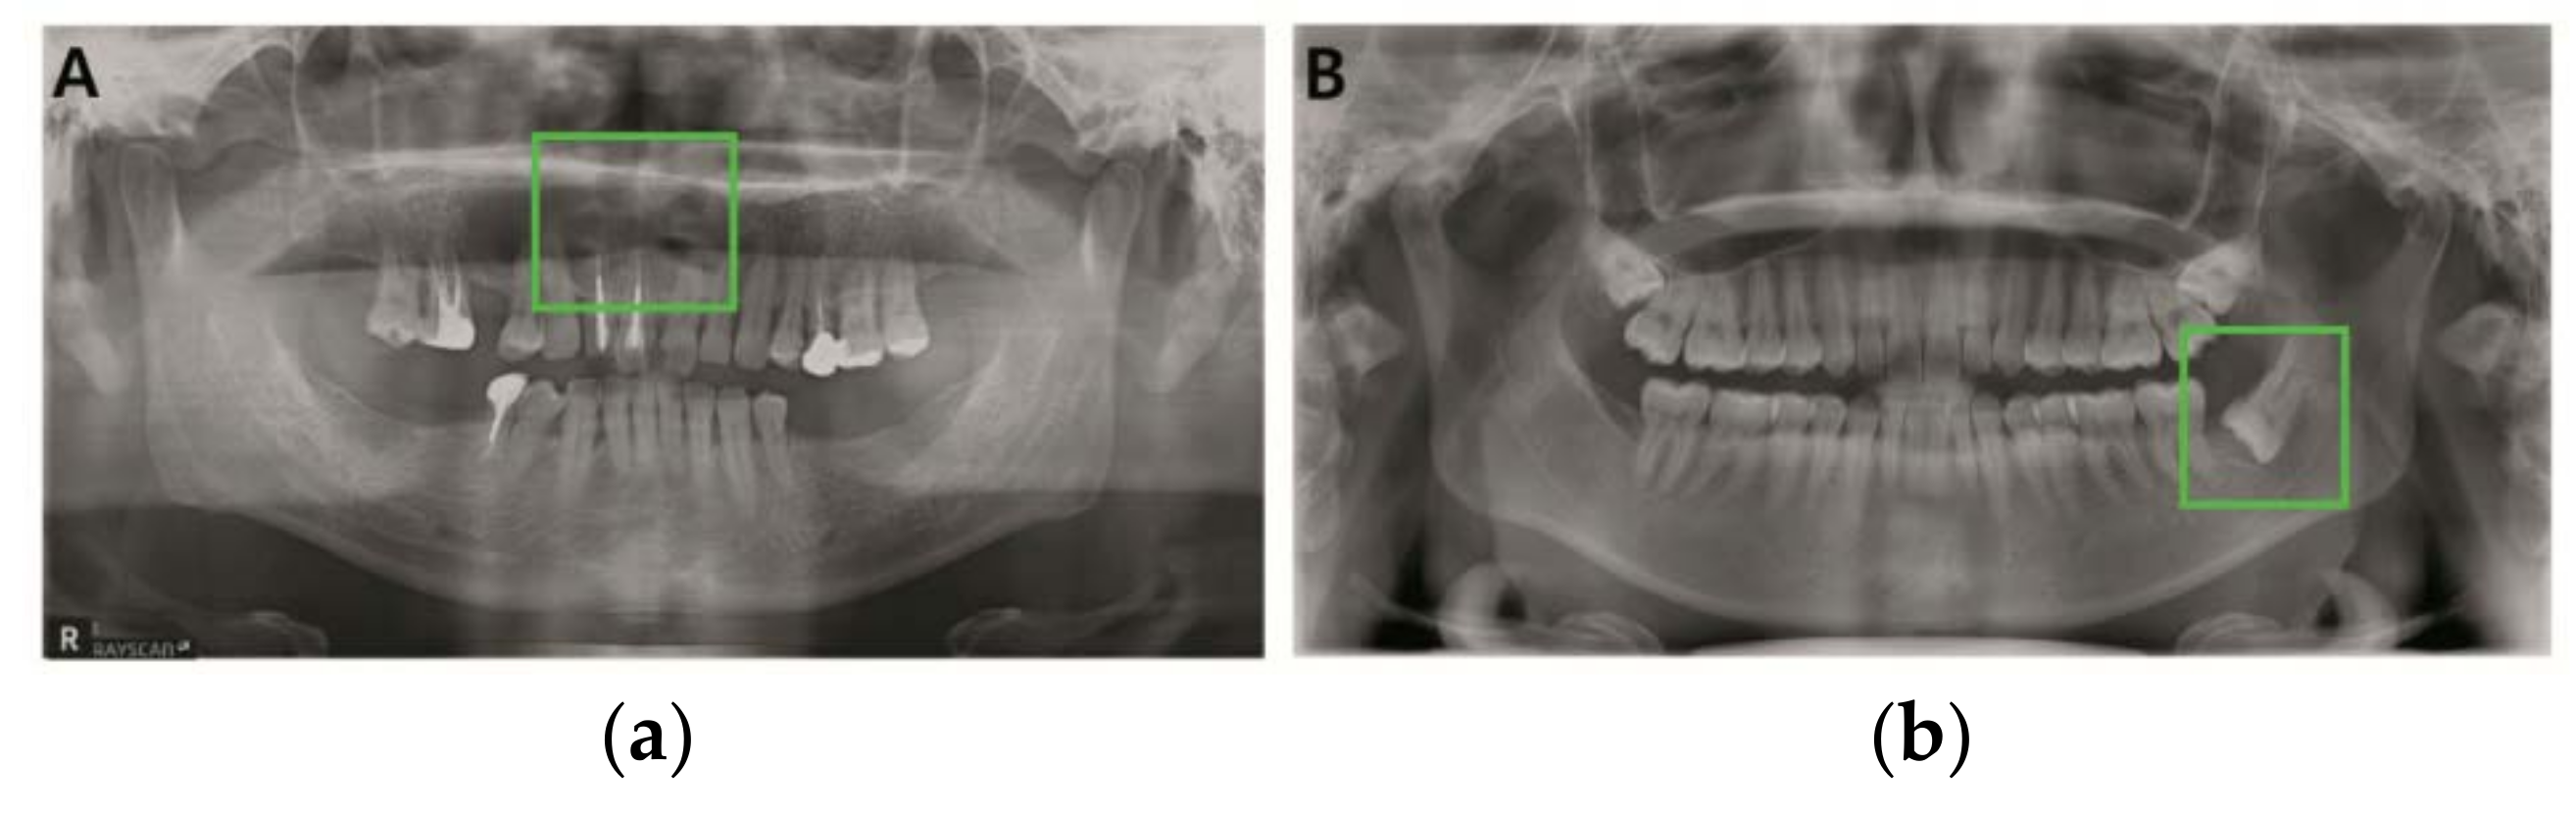

3.2. Detection Results